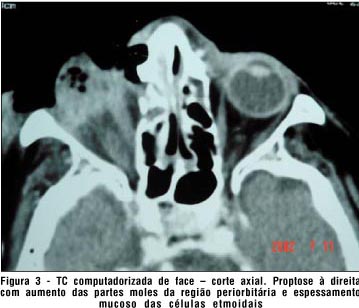

A tomografia computadorizada de crânio e órbitas mostrou extensa lesão ulcerada, profunda, localizada no assoalho orbitário direito, com acentuado acometimento das estruturas intra-orbitárias adjacentes; importante destruição do globo ocular; esclerose óssea do arco zigomático; espessamento mucoso do seio maxilar, células etmoidais, fossas nasais e conchas nasais à direita. Havia solução de continuidade na lâmina papirácea direita. Não havia sinais de extensão intracraniana (Fig. 2 e 3).